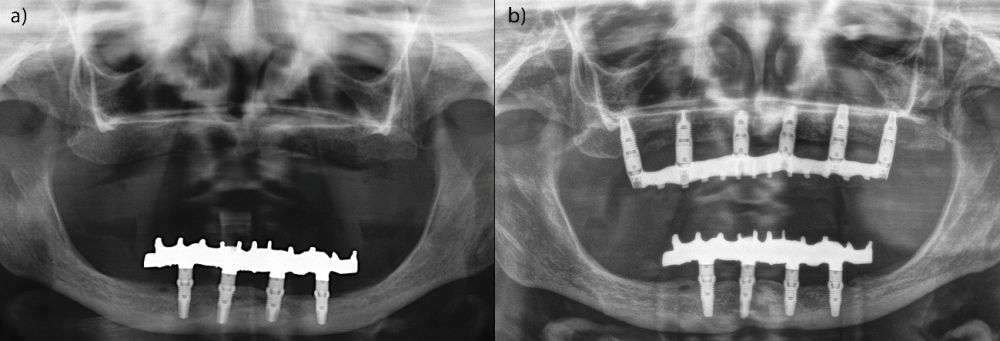

El análisis global de los 99 implantes reveló una pérdida ósea marginal media de 0,77 ± 0,26 mm en la superficie mesial y 0,79 ± 0,29 mm en la distal, valores que se mantuvieron dentro de los rangos considerados clínicamente aceptables para rehabilitaciones mandibulares. Cuando los implantes se categorizaron según su longitud, se observaron diferencias claras entre ambos grupos. Los implantes cortos (<10 mm) mostraron una pérdida ósea mesial media de 0,61 ± 0,23 mm y distal de 0,56 ± 0,22 mm, mientras que los implantes largos (≥10 mm) presentaron pérdidas significativamente mayores (mesial: 0,92 ± 0,19 mm; distal: 0,99 ± 0,17 mm). Dado que las pruebas de normalidad (Shapiro–Wilk) mostraron una distribución no normal en todos los grupos (p < 0,001), se aplicó la prueba no paramétrica de Mann–Whitney U. Los resultados confirmaron diferencias estadísticamente significativas tanto en la pérdida ósea mesial (U = 2068,5; p < 0,001) como en la distal (U = 2247,0; p < 0,005), indicando que los implantes cortos presentaron un comportamiento óseo más favorable que los implantes largos a lo largo del tiempo. Durante el tiempo de seguimiento que fue de media de 12,2 años (+/- 4,4; rango 6-23 años) no se objetivaron fracasos en ninguno de los implantes por lo que la supervivencia acumulada fue del 100%. El análisis del periodo de seguimiento mostró diferencias claras entre ambos grupos. Los implantes largos (≥10 mm) presentaron un tiempo medio de función de 14,1 ± 4,2 años (rango: 9–23 años), mientras que los implantes cortos (<10 mm) registraron un seguimiento significativamente menor, con una media de 9,8 ± 2,7 años (rango: 6–15 años). En las Figuras 3- 10 se muestran dos casos incluidos en el estudio, uno de cada situación descrita.

Un aspecto clave para interpretar estos resultados es el tiempo de seguimiento, ya que en nuestra cohorte los implantes largos presentaron significativamente más años en función intraoral. El análisis del periodo de seguimiento mostró diferencias claras entre ambos grupos. Los implantes largos (≥10 mm) presentaron un tiempo medio de función de 14,1 ± 4,2 años (rango: 9–23 años), mientras que los implantes cortos (<10 mm) registraron un seguimiento significativamente menor, con una media de 9,8 ± 2,7 años (rango: 6–15 años). La comparación mediante la prueba de Mann–Whitney U reveló diferencias estadísticamente significativas entre ambos grupos (p < 0,001). Este mayor tiempo en función de los implantes largos constituye un factor relevante a considerar en la interpretación de las diferencias observadas en la pérdida ósea marginal. La literatura demuestra que la pérdida ósea crestal es más pronunciada durante los primeros 12 meses y tiende a estabilizarse posteriormente, aunque existe un remodelado lento y continuo asociado al tiempo 36,48–50. Por tanto, es plausible que parte de la mayor pérdida ósea observada en los implantes largos esté relacionada con el mayor periodo de observación, aunque con los datos y el análisis realizado en el presente estudio, no podemos establecer esta correlación. Este factor debe considerarse al comparar ambos grupos y será analizado en estudios futuros con modelos de regresión ajustados por tiempo.

Por otro lado, la ausencia de fracasos implantares en ambos grupos es especialmente destacable, ya que la rehabilitación completa sobre cuatro implantes ha sido históricamente objeto de preocupación biomecánica, tanto por la carga concentrada como por la presencia potencial de cantilevers en las prótesis12,15. En técnicas como el All-on-4 descrito por Malo, donde los implantes distales se angulan 30–45°, se han reportado supervivencias elevadas, pero también mayores tasas de complicaciones mecánicas y protésicas, especialmente relacionadas con la sobrecarga distal y la fatiga del tornillo o de la estructura13,47. En contraste, la estrategia utilizada en este estudio, basada en cuatro implantes paralelos, cortos o largos según la disponibilidad ósea, reduce la complejidad biomecánica y distribuye las cargas de forma más homogénea, minimizando los momentos de flexión sobre los implantes distales18. La capacidad de los implantes cortos para sostener rehabilitaciones completas ha sido respaldada por múltiples estudios. Diferentes trabajos de la literatura internacional han demostrado que los implantes cortos (≤8 mm) alcanzan supervivencias comparables a los convencionales y presentan tasas similares de complicaciones mecánicas, siempre que se respeten principios biomecánicos como la ferulización rígida, la correcta pasividad protésica y la ausencia de cantilevers excesivos21,22,35–41,51–56. Los resultados de este estudio refuerzan esta evidencia, mostrando que los implantes cortos no solo no incrementan la pérdida ósea, sino que pueden presentar un comportamiento marginal más estable en el largo plazo.

En relación con el voladizo, en nuestra cohorte únicamente las prótesis soportadas por implantes largos presentaban un mayor cantilever distal, mientras que las rehabilitaciones basadas en implantes cortos no lo requerían o tenían uno de longitud mínima. La literatura indica que la presencia de cantilever puede aumentar de forma significativa las tensiones sobre los implantes distales y favorecer el remodelado óseo marginal12,15,57–60. Este hecho podría contribuir a explicar las mayores pérdidas óseas del grupo de implantes largos, al margen del dato del tiempo de seguimiento anteriormente discutido y subraya la relevancia clínica de planificar rehabilitaciones sin voladizo siempre que la anatomía y los implantes cortos lo permitan. Finalmente, la estabilidad de las rehabilitaciones en ambos grupos confirma que el protocolo estandarizado aplicado en esta serie constituido por fresado biológico, carga progresiva y estructura híbrida atornillada sobre transepitelial, con implantes siempre paralelos, sin inclinaciones distales, proporciona un entorno favorable para la osteointegración y el mantenimiento periimplantario a largo plazo. Este enfoque coincide con las tendencias actuales hacia tratamientos mínimamente invasivos, pero biomecánicamente sólidos, reduciendo la necesidad de angulaciones extremas o regeneraciones complejas sin comprometer los resultados clínicos30,32,61,62.